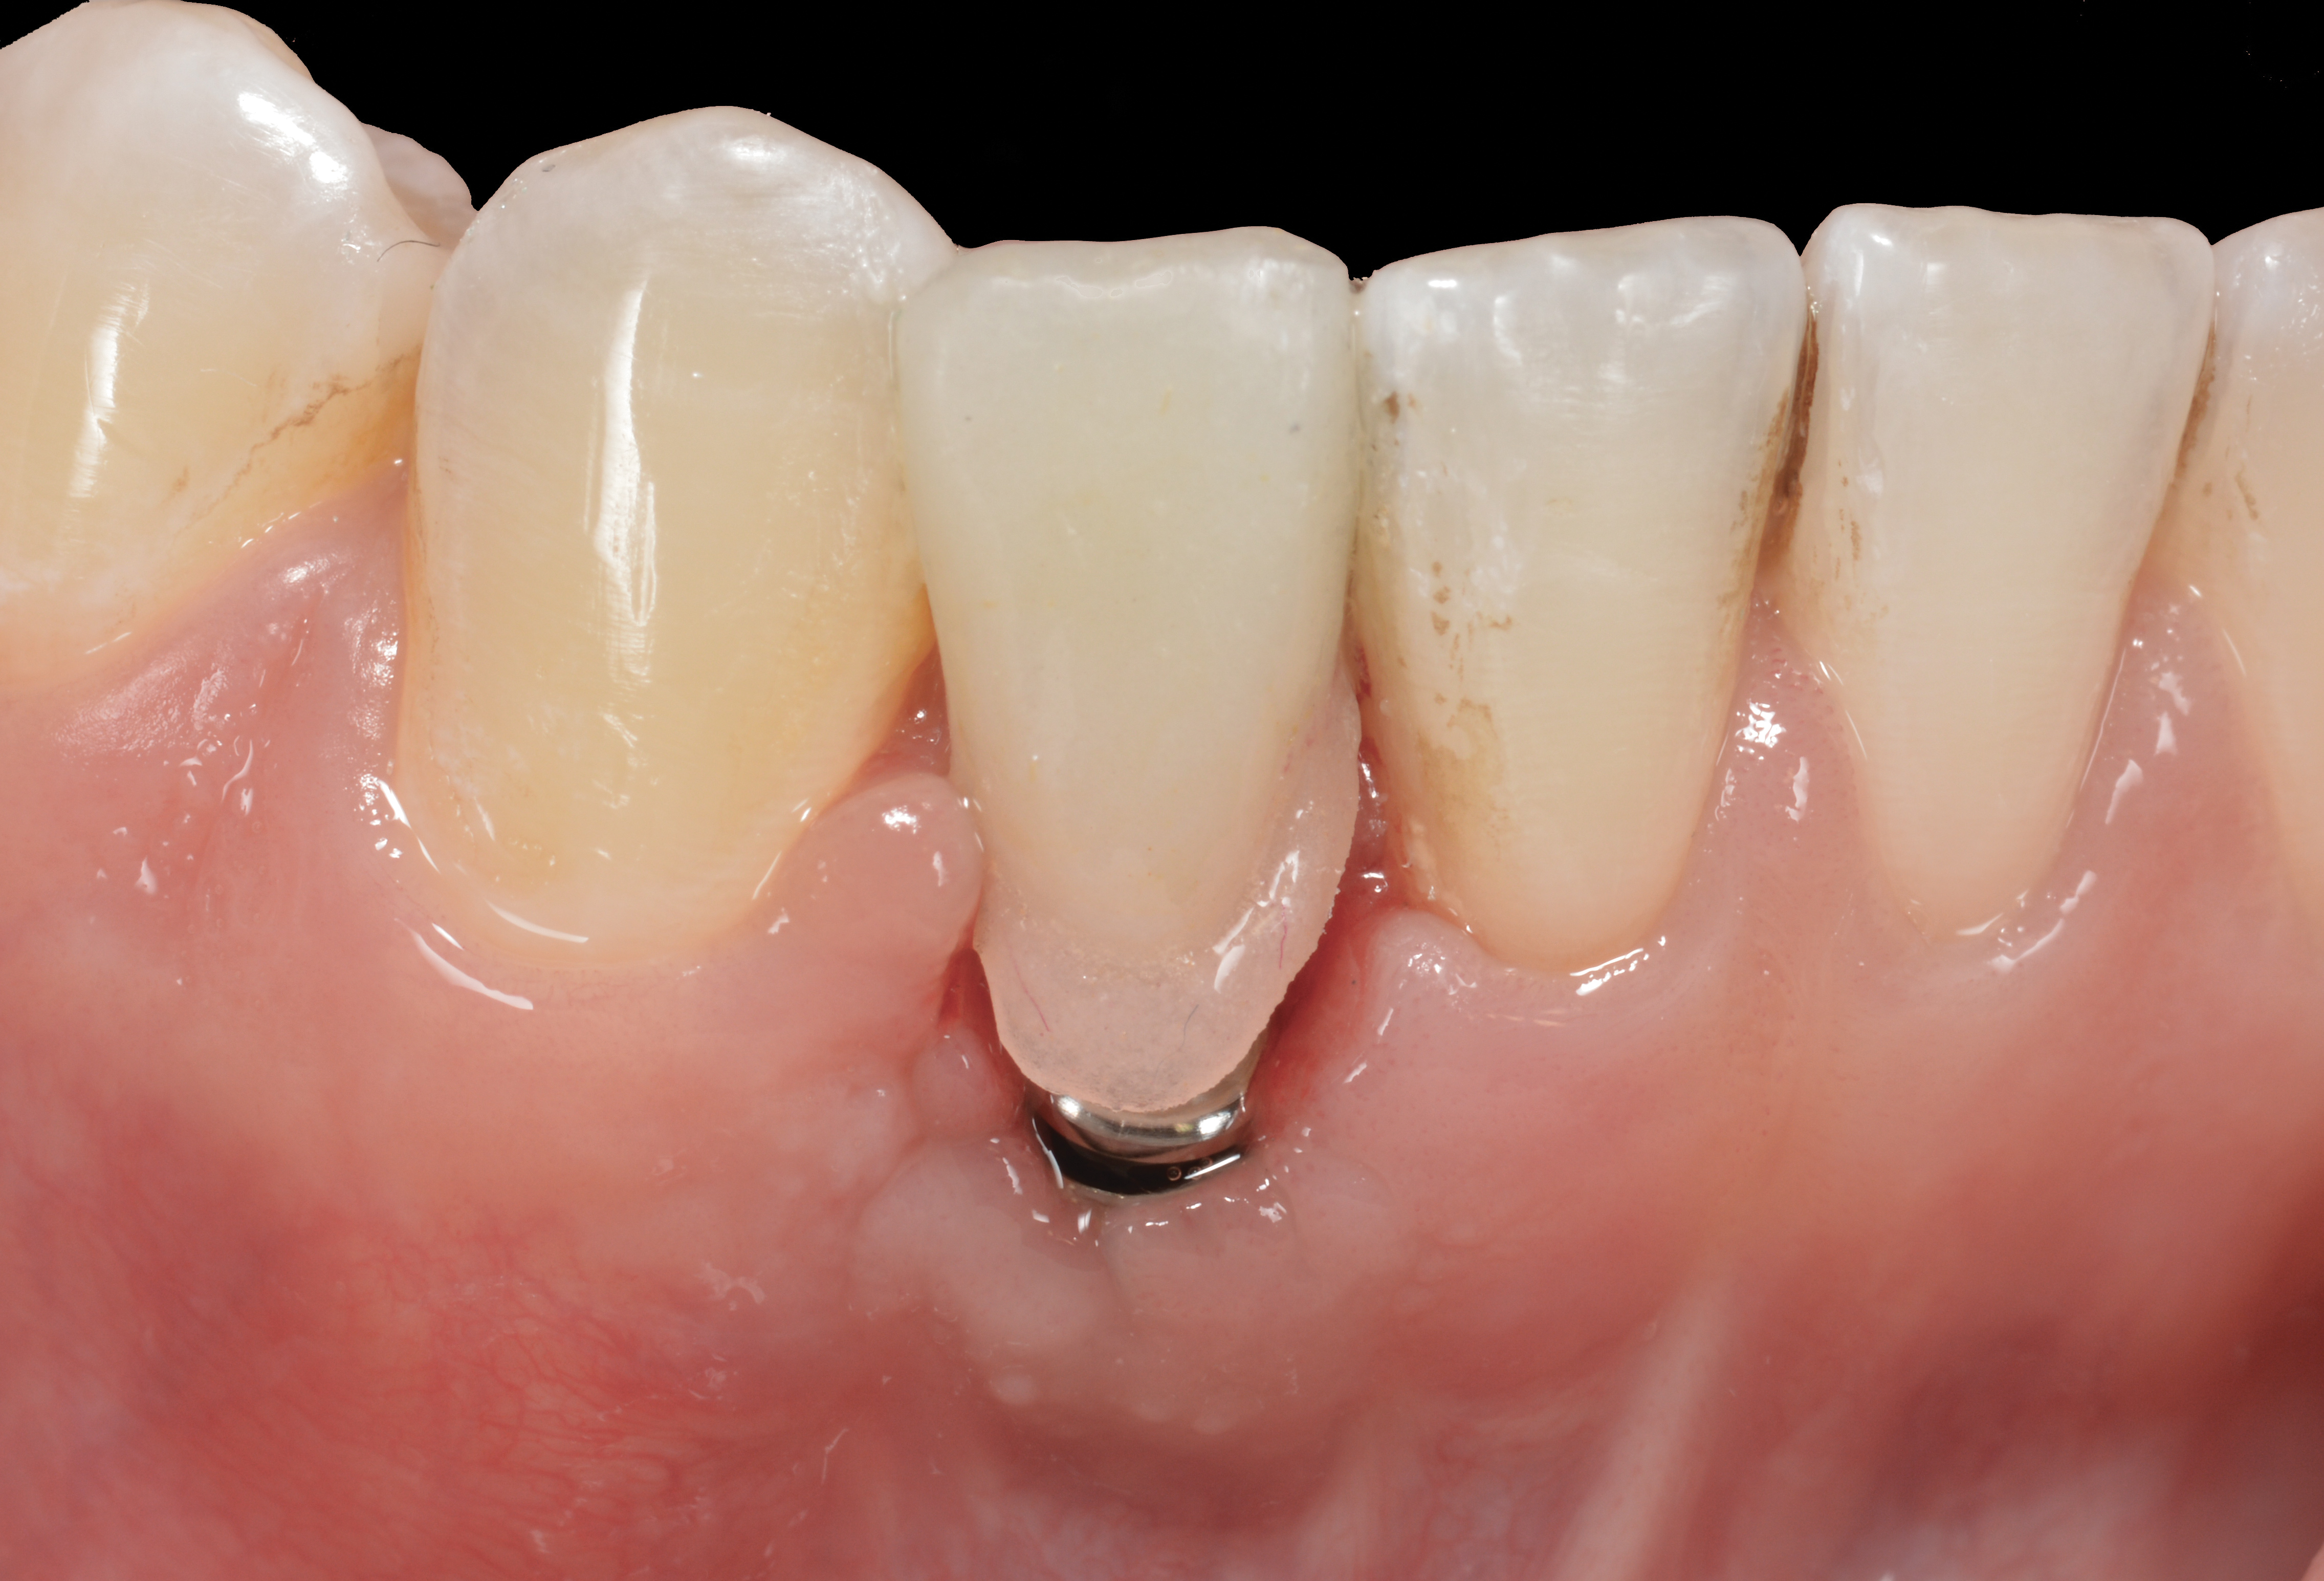

Fig 3. A patient presented with a high smile line and midfacial recession of the maxillary right lateral incisor as evidenced by the increased tooth length compared with the contralateral lateral incisor.

Figure 3

Fig 4. Intraoral view of tooth No. 7 with the gingival zenith more apical than the adjacent central incisor and canine tooth.

Figure 4